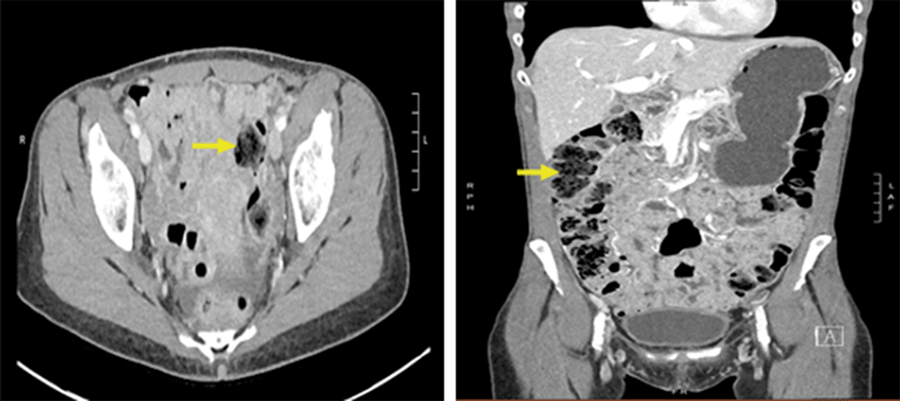

Figure 1. Axial (left) and Coronal (right) Section of CT with Intravenous Contrast on Day of Initial Presentation. Published with Permission

CT scan shows no acute intraabdominal pathology two weeks prior to intussusception. Additionally, there are no signs of obstruction or inflammatory process despite mild stool burden throughout colon (arrow).